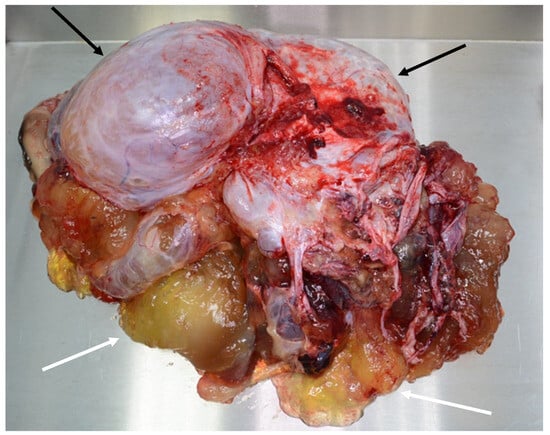

Figure 10. Ruptured mucocele of the appendix in perioperative view. Part of the appendix (black arrow) is embedded in mucus (white arrow), which covers the perforation.

The mucocele ruptures due to increased intra-appendicular pressure, releasing mucus and tumor cells into the peritoneal cavity (Figure 9 and Figure 10). The rupture may be asymptomatic or associated with only mild and nonspecific clinical signs. Typical peritoneal signs and bacterial peritonitis are usually absent because the communication to the lumen of the colon is closed by mucin. Treatment in these cases is called a radical appendectomy, with the resection of the cecal bases, but without a right colectomy. The addition of HIPEC is fully indicated. It is necessary to examine the whole abdomen to exclude the presence of tumors in typical locations, such as the Douglas pouch and the undersurfaces of the diaphragm and the right and left paracolic gutter.